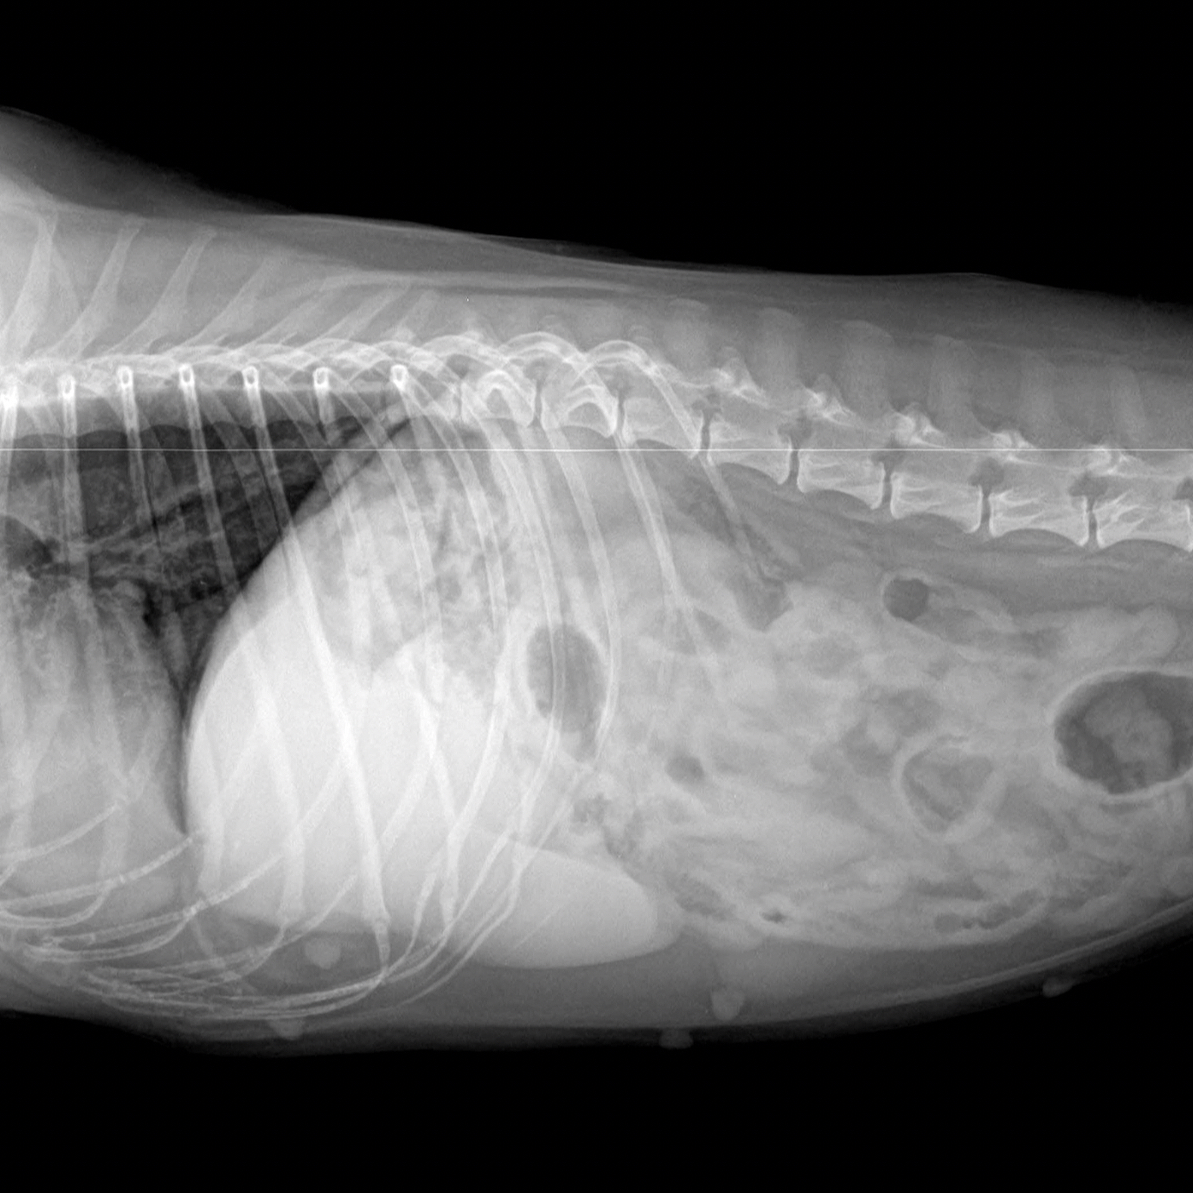

Veterina VeMaP nabízí profesionální a lidský přístup k pacientům i jejich majitelům. Ordinace se zaměřuje na individuální péči, klidnou atmosféru a minimalizaci stresu zvířat. Věnuje se nejen preventivní péči, diagnostice a léčbě, ale také specializovaným službám, například stomatologii, chirurgii měkkých tkání v humánním standardu vč. komplexních anesteziologických služem - zkušený anesteziolog na sále, kardiologii nebo etologii. Součástí týmu jsou zkušení veterinární lékaři i specialisté na problematiku chování zvířat. VeMaP využívá moderní přístroje, pravidelně se vzdělává a spolupracuje s předními pracovišti u nás i v zahraničí. Klienti si chválí přátelský servis, objednávkový systém a dlouhé ordinační hodiny, včetně víkendů a svátků.